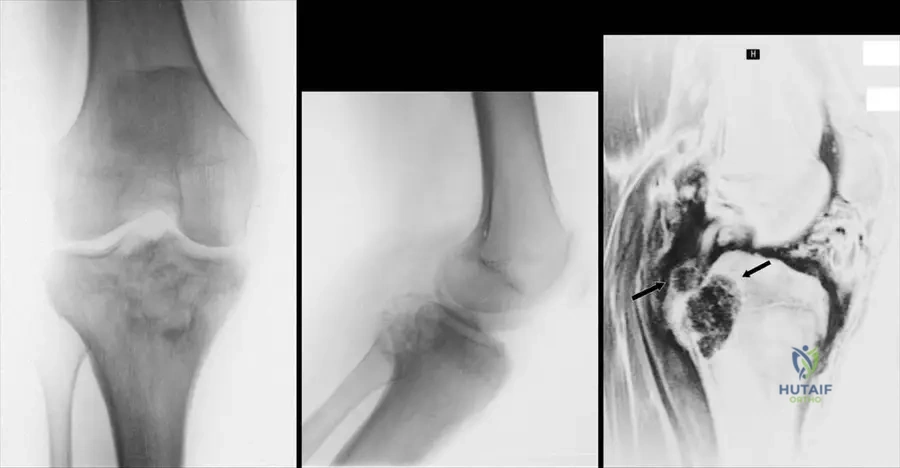

A 48-year-old male presents with a firm mass in his lower leg. MRI is performed to assess the lesion's relationship to surrounding structures.

Correct Answer: A

Rationale: The clinical context for Fig. 9.17 states: "Proton density (a), T2 (b), images of the lesion. Note the heterogeneity and intimate association with the fibula." Main Distractor: B) Tibia. While the tibia is in the lower leg, the text specifically mentions the "intimate association with the fibula" for this particular image.